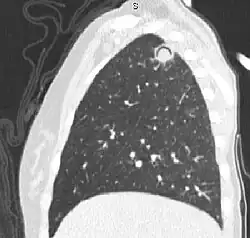

In radiology, the air crescent sign (also called the Monad sign[1]) is a finding on chest radiograph and computed tomography that is crescenteric and radiolucent, due to a lung cavity that is filled with air and has a round radiopaque mass.[2] Classically, it is due to an aspergilloma, a form of aspergillosis, that occurs when the fungus Aspergillus grows in a cavity in the lung.[3]